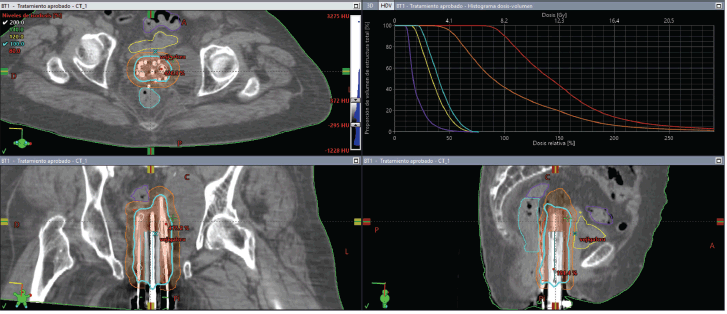

The initial plan suggested possible undercoverage in superficial regions of the tumour (Figure 3). Therefore, a custom silicone bolus containing four additional catheters was placed on the vulvar surface to enhance coverage of peripheral edges. A repeat CT confirmed improved D100 and D90 of the GTV while maintaining urethral dose constraints (Table 1, Figure 4).

Figure 4. Case 1. 3D treatment plan with bolus. The position of the catheters and the dosimetric distribution in the axial, coronal and sagittal planes are observed. On the left, fraction #2 to #5. On the right, fraction #6 to #8. In light blue, the isodose of 5.7 Gy; in white, the isodose of 11.4 Gy.